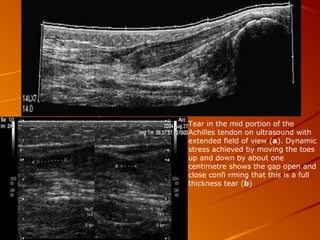

Tear in the mid portion of the

Achilles tendon on ultrasound with

extended field of view (a). Dynamic

stress achieved by moving the toes

up and down by about one

centimetre shows the gap open and

close confi rming that this is a full

thickness tear (b)